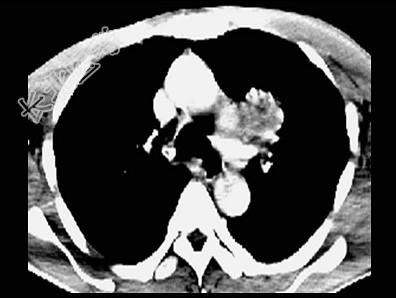

- 单项选择题男,58岁, 头痛、恶心、行走不稳,肺和脑CT检查如图, 最可能的诊断为 ( )

C、肺癌脑转移